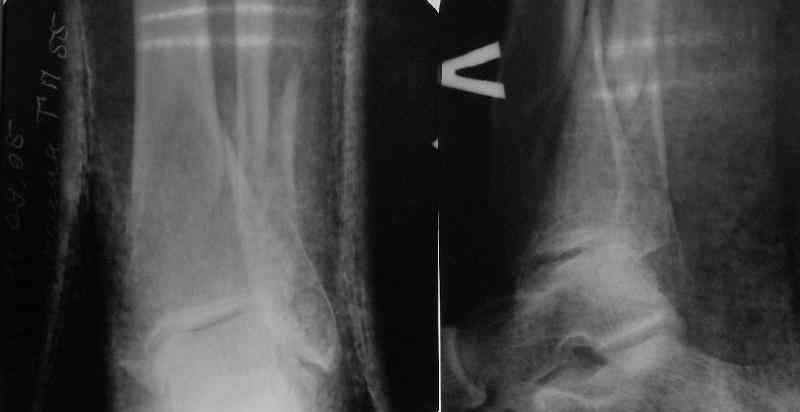

TDVC> Very interesting application, but is the final position in a

TDVC> little distal varus with some fibula distraction?

At least both the ankle mortise and tibial alignment look acceptable, don't they?

In delayed cases acute length restoration performed only in the tibia may leave the fibula shortened thus change the mortise. So it is reasonable to restore length of both bones simultaneously by distractor and fix the fibula not with open reduction and plating but just by a single perQ screw. Example attached.